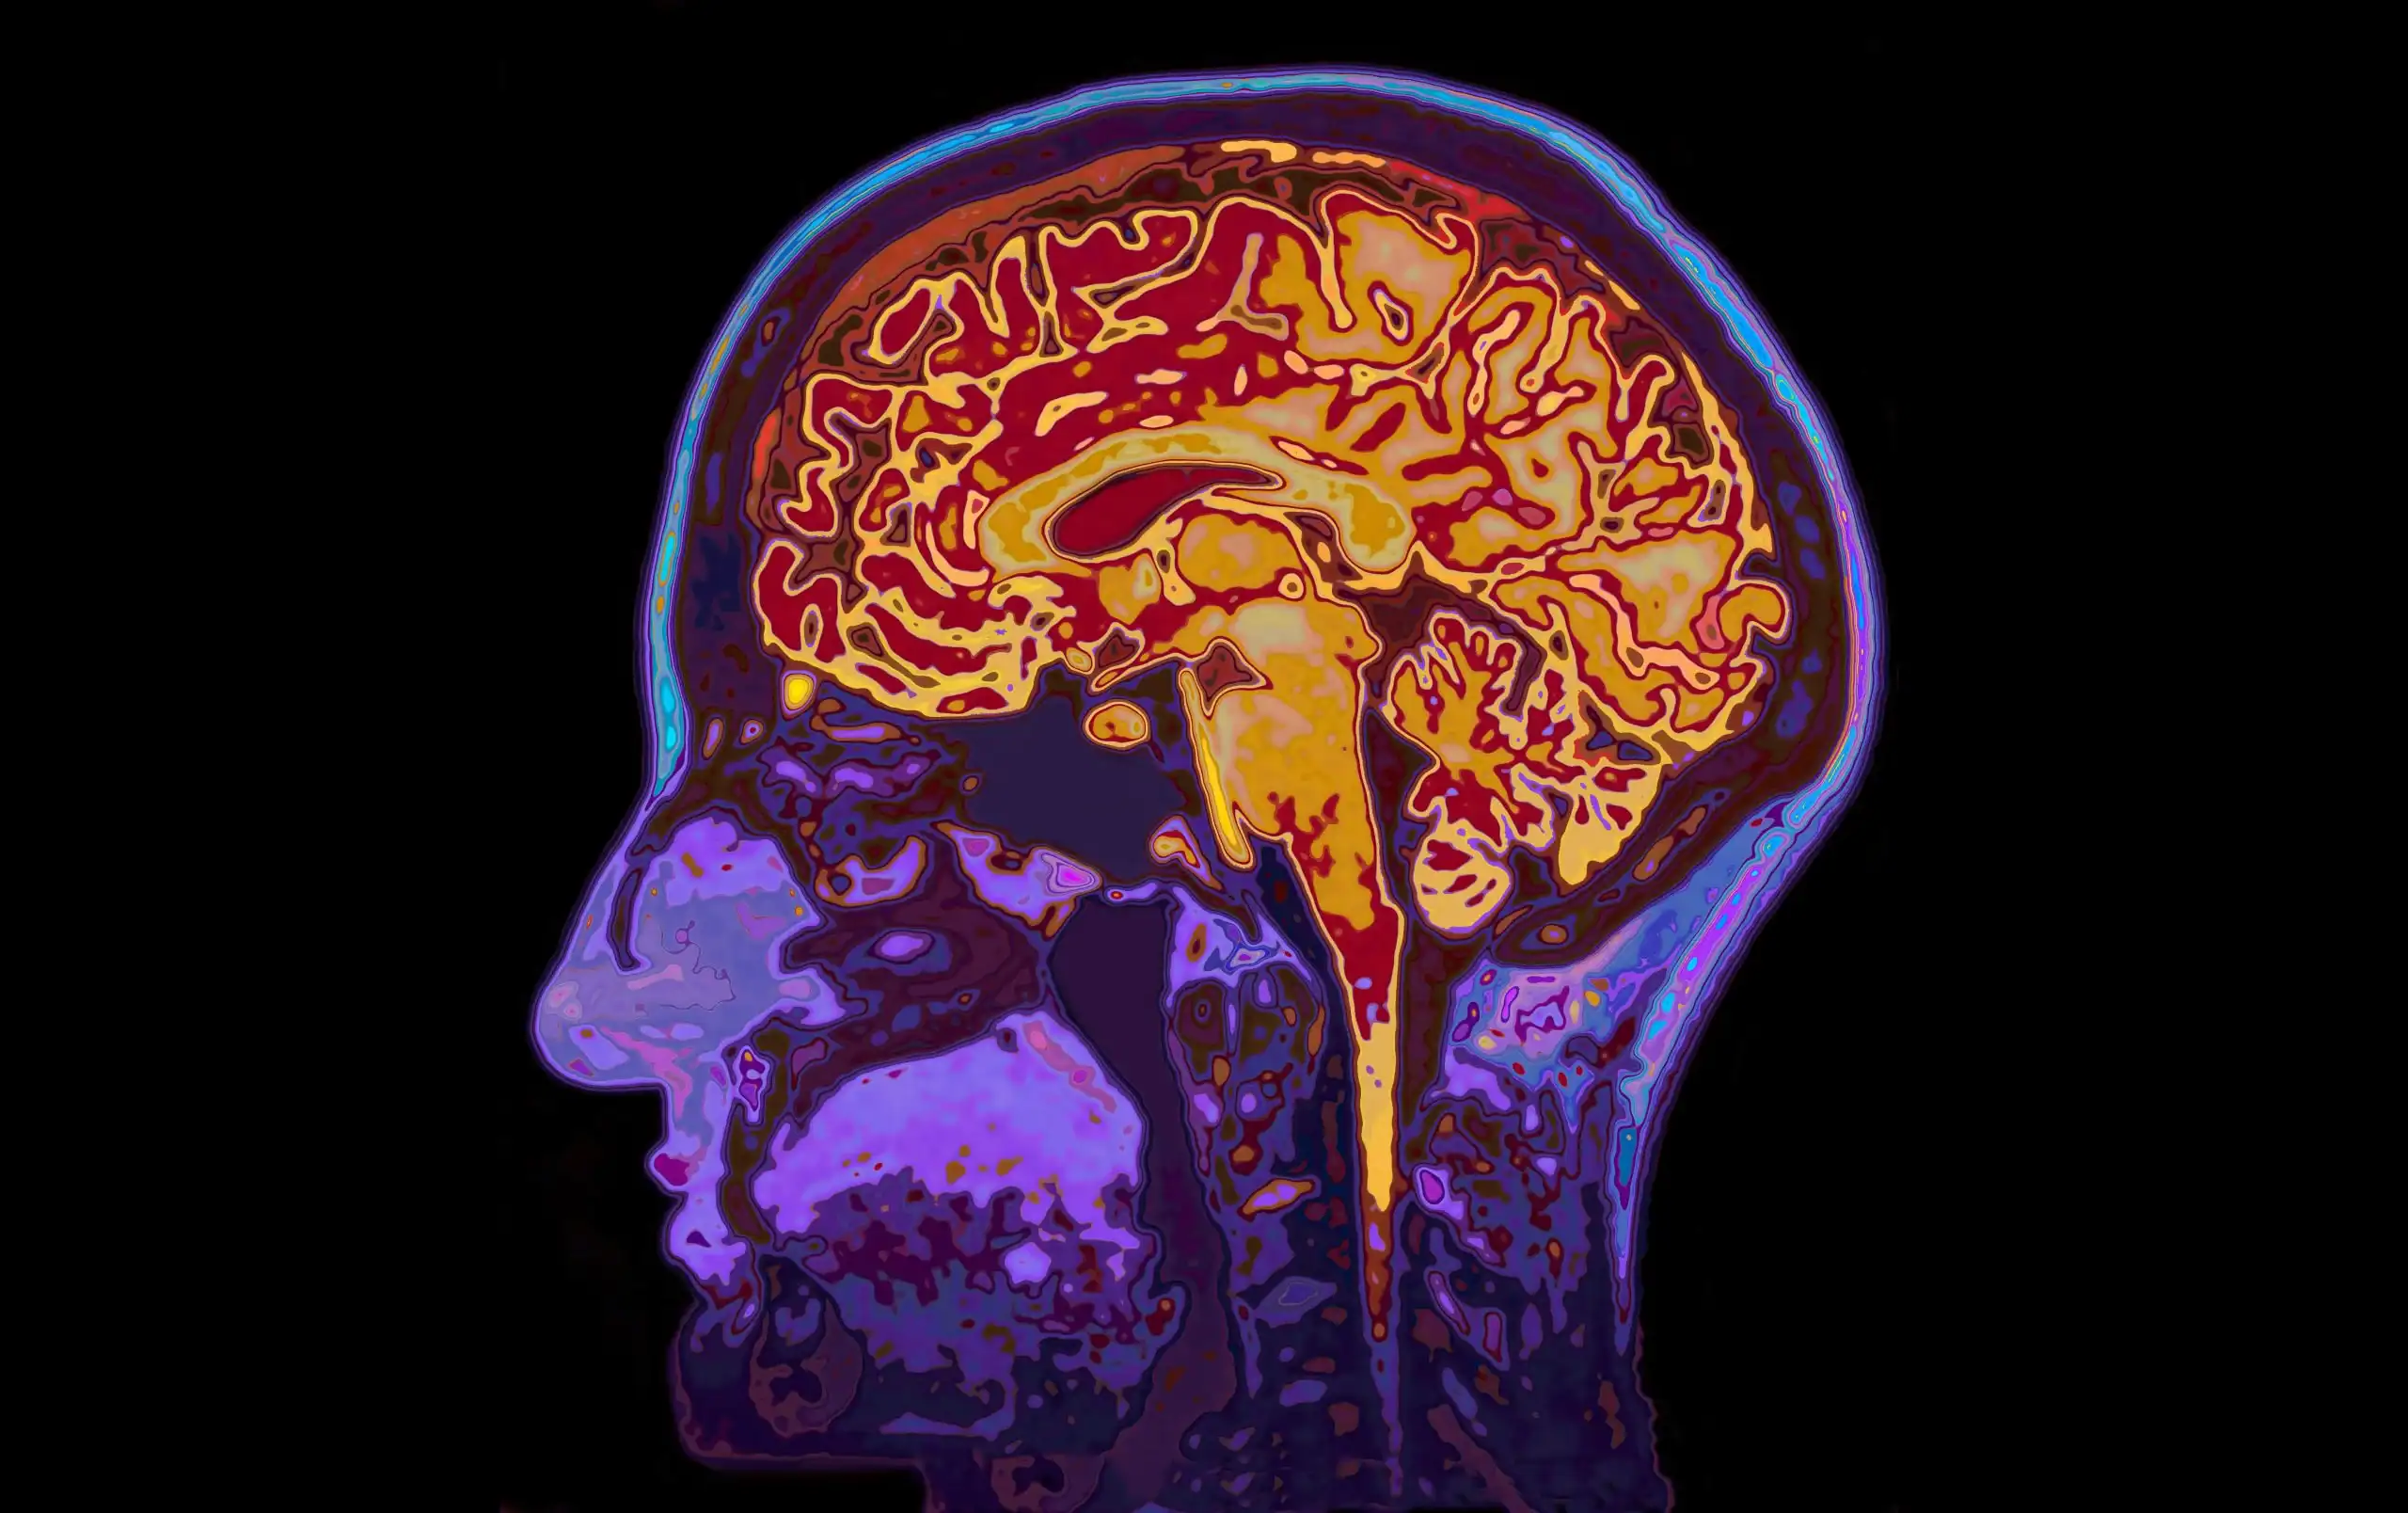

Un team giapponese ha sviluppato il "mind captioning", un metodo che genera descrizioni testuali di immagini "percepite" o immaginate dal cervello, basandosi sull'attività cerebrale rilevata tramite MRI e successivamente elaborata tramite IA. Il sistema traduce quindi l'attività neurale in linguaggio, funzionando anche per i ricordi visivi.

- Ricercatori giapponesi del NTT Communication Science Laboratories, guidati da Tomoyasu Horikawa, hanno sviluppato il "mind captioning", un metodo per generare testo descrittivo dall'attività cerebrale umana.

- Il sistema rileva l'attività cerebrale tramite scanner MRI mentre i volontari guardano video e la traduce in descrizioni testuali utilizzando l'intelligenza artificiale.

- Un'intelligenza artificiale è stata addestrata per collegare i dati cerebrali a "firme semantiche", ovvero rappresentazioni numeriche di significato, create da sottotitoli video elaborati da modelli linguistici.

- Successivamente, un altro modello linguistico genera frasi complete a partire da queste firme semantiche, affinando la descrizione attraverso un processo iterativo di sostituzione delle parole.

- Il "mind captioning" si è dimostrato efficace anche quando i volontari immaginavano i video, suggerendo che il cervello usa rappresentazioni simili per vedere e ricordare visivamente.

- La capacità del sistema di generare testo persiste anche escludendo le aree cerebrali tradizionalmente associate all'elaborazione del linguaggio, indicando che il significato è distribuito ampiamente nel cervello.

- Questa tecnologia offre potenziali applicazioni per la comunicazione in persone affette da afasia o malattie neurodegenerative che compromettono la parola, fungendo da "interfaccia interpretativa".